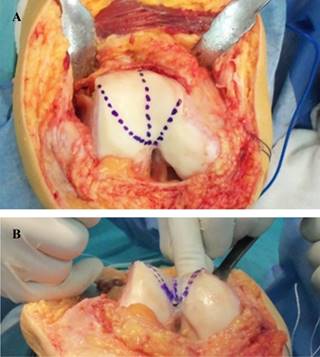

La rótula es evertida para la inspección de posibles lesiones osteocondrales tanto femorales como rotulianas y luego se retrae lateralmente, exponiendo y reconociendo el morfotipo troclear a tratar. Teniendo como objetivo principal disminuir la prominencia troclear y crear un nuevo surco de profundidad y vertientes anatómicos, se realiza la trocleoplastía planificada (Figuras 7 y 8). El procedimiento es completado con una reconstrucción del ligamento patelofemoral medial utilizando un injerto de tendón semitendinoso, el cual se tuneliza a través de la rótula y se fija en el punto de isometría femoral con un tornillo de interferencia.

Figura 7: A) Imagen intraoperatoria de una paciente de 37 años previamente a la trocleoplastía. B) Mismo caso luego de realizar la trocleoplastía.

En el trazado de la nueva tróclea el surco troclear queda referenciado por la muesca intercondílea, desde donde se dirige de manera proximal y de 3o a 6o lateralmente; los márgenes anteriores están demarcados por la unión osteocondral, que es un hito constante. Al exponer la tróclea femoral, el periostio peritroclear y la sinovial se inciden desde la unión medial hasta la osteocondral lateral. Luego se expone el hueso esponjoso supratroclear alrededor del perímetro proximal de la tróclea. El ancho de esta exposición ósea corresponde a la prominencia de la tróclea (distancia entre la corteza anterior del fémur y el límite del cartílago troclear).

Se retira un poco de hueso esponjoso con una cureta y fresas graduadas. Se debe tener mucho cuidado para no causar daño térmico al cartílago o al hueso subcondral. Se extrae más hueso debajo de la porción central de la tróclea que en sus vertientes laterales. Las carillas trocleares se impactan y se estabilizan utilizando tres arpones (uno en el intercóndilo y los otros dos sobre cada carilla troclear respectivamente). Antes dividimos cada carilla articular con un corte utilizando un bisturí.